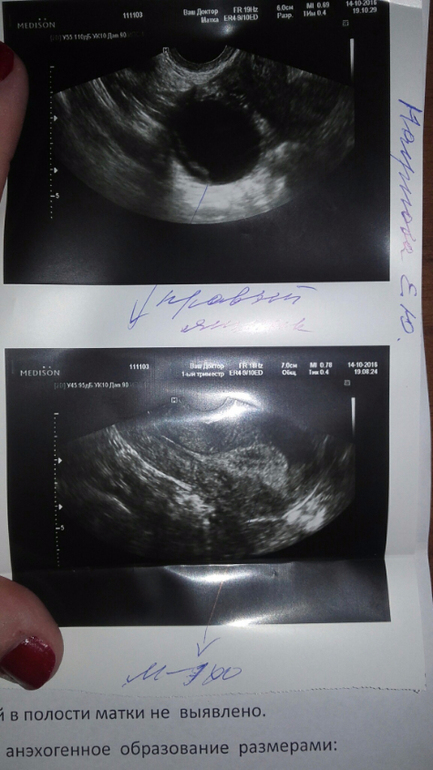

Не везет мне по жизни...Вчера ездила на узи.Нет у меня Б..Нету..Сказали даже намека нет.Пипец.Устала я уже от всего.Лежала на стационаре.На выходные отпустили.Моя врач ставит Б.5-6 недель.В понедельник на учет ставит.Вот как?Я в полном шоке..Какие хочется закричать недели.Там пусто.И я пустая.Нету у меня Б..Нету.Наверное и не будет уже.Что за несправидливость такая.Кто то на аборты бегает..А тут ну ни как совсем.Ставят кисту.Девочки возможно ли с ней вообще забеременнеть?Врач Б не исключает..Сказала каждое утро делать тесты.Сдала на ХГЧ вчера.Ответ в среду только.Вот такой у нас каменный век.Сказала ждать М.Но у меня ни чего не болит..Не тянет..Вообщем пипец какой то

киста фолликулярня, с месячными уйдет. я бы после того как хгч исключит Б, начала бы пить дюфастон чтоб вызвать побыстрее М.

ну а то что киста фолликулярная образовалась, это вам толчек к тому чтоб походить на фолликулометрию и сдать на гормоны. Возможно вам просто нужен укол ХГЧ для разрыва в предовуляторной фазе. Тем более что эндометрий у вас шикарный

Хгч прояснит ситуацию. Мне в первую Б на узи поставили кисту двухкамерную и еще куча болячек нашли типа. Б не увидели. Г на осмотре тоже Б не нащупала, сказала, что матка из-за кисты увеличена и давай меня лечить. Ну раз мне Б исключили аолностью я хгч не сдавала и тесты не делала. Вот так я и узнала только на 7 нед.

Сейчас у меня опять такая же ситуация. На узи кисту видят. Б и ВБ по узи нет А тесты полосатить начали, слабенько но есть. Пойду хгч сдавать.